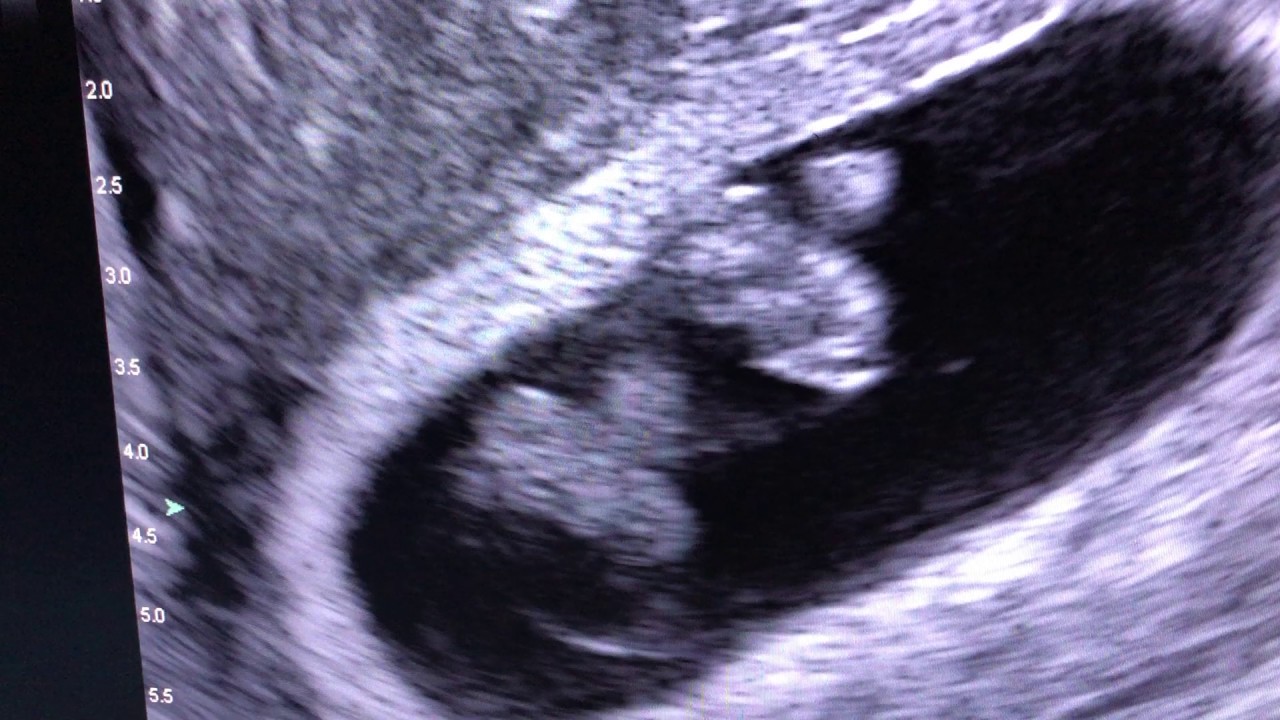

Scan of the Week Twins at 9 weeks gestation! YouTube

Scan of the Week Twins at 9 weeks gestation! YouTube What Do Twins Look Like On An Early Ultrasound Early ultrasounds are usually held between 6 and 8 weeks of pregnancy, while. Signs of a twin pregnancy could include feeling early pregnancy symptoms more intensely, but there isn’t really any way to really. Most patients have their first. How early can you see twins on an ultrasound? The earliest you can typically expect to see twin fetuses on an. What Do Twins Look Like On An Early Ultrasound.